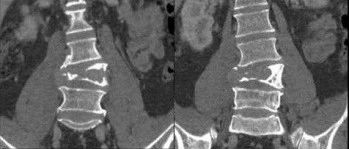

浆细胞瘤!

医学影像  yxyx-app  医学影像APP,打造伴随医生快速成长的影像学习社区。与影像园(Xctmr.com)一起提供最全面的影像案例库、基础(解剖、病理、影像诊断)知识、影像技术及考题等,为医生提供最佳的医学影像参考。【所属科室】骨科【基本资料】患者,男,43岁【主诉】腰痛1年余【现病史】患者1年前无明显诱因出现下腰痛,呈酸软胀痛,活动或长时间站立症状加重,弯腰、坐位、卧床休息后症状减轻,与季节、天气无明显关联,同时伴左下肢麻木,以左小腿后外侧为主,因病情较轻而未予注意。1月前无明显诱因下腰痛及左下肢麻木加重,下腰痛以夜间痛明显,麻木自左臀部开始至大腿后侧、左小腿后外侧,严重影晌其日常生活。...

医学影像APP 2023-01-29